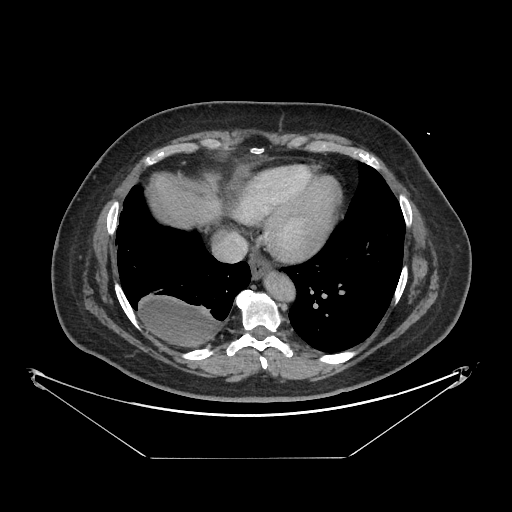

Reconstructed NATIVE CT scan (cycle consistency)

Full window (WL 1023.5, WW 4095 β†’ Low βˆ’1024, High +3071)

Actual HU range: [-1024.0, 631.9]

Lung window (WL -600, WW 1500 β†’ Low βˆ’1350, High +150)

Actual HU range: [-1150.5, 150.0]

Mediastinum window (WL 40, WW 400 β†’ Low βˆ’160, High +240)

Actual HU range: [-160.0, 240.0]